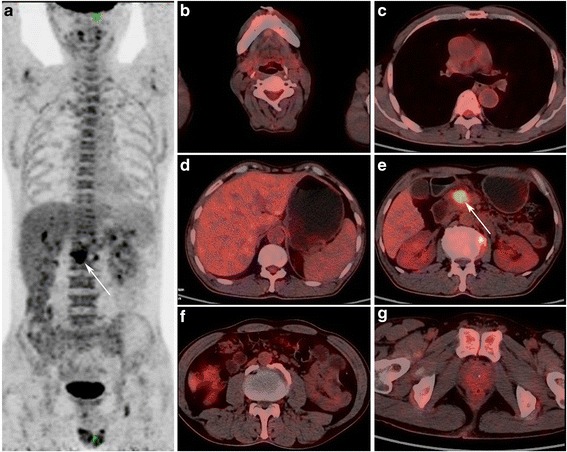

Fig. 2.

A 66-years old male patient with focal AIP in the pancreatic head. MIP PET (a) and PET/CT fusion (e) images shows localized enlargement of the pancreatic head with increased FDG uptake (arrow), with early and delayed SUVmax of 6.7 and 8.0, respectively. PET/CT fusion images shows (b) increased FDG uptake in bilateral submandibular gland, with a SUVmax of 7.9; (c), enlargement of mediastinal lymph node with increased FDG uptake (SUVmax, 5.7); (d), dilatation of bile duct; (f), retroperitoneal fibrosis around artery; (g) inverted “V” shaped high FDG uptake in the prostate

Fig. 3.

A 59-years old male patient with pancreatic cancer. MIP PET (a) and PET/CT fusion (e) images show a mass in the pancreatic head with increased FDG uptake (arrow), with early and delayed SUVmax of 9.3 and 10.8, respectively. Compared with AIP patients in Fig. 2, no increased FDG uptake foci in the salivary gland b), mediastinal lymph nodes (c), retroperitoneal space (f), and prostate (g) are observed, as well as no bile duct expansion (d)